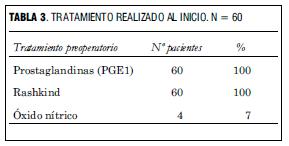

En todos los casos se instaló infusión intravenosa continua de prostaglandinas (PGE1), para asegurar la permeabilidad ductal y luego de lograda la estabilización se realizó atrioseptostomía con catéter-balón en sala de hemodinamia (Rashkind). A los pacientes que ingresaron en gasto bajo e hipoxemia se les realizó dicho procedimiento de urgencia con buena evolución.

Cuatro pacientes requirieron el aporte de óxido nítrico (NO) por presentar hipertensión pulmonar persistente y no mejorar la saturación arterial de oxígeno a pesar de una adecuada atrioseptostomía (tabla 3).

Todos se presentaron con hipoxemia y 25% presentó, además, signos de bajo gasto. Dos tercios eran D-TGA simples y un tercio se presentaron como D-TGA complejas (todas con comunicación interventricular) asociando coartación de aorta e hipoplasia del arco aórtico en un caso, estenosis subpulmonar leve en un caso y situs inversus en un caso. En 76% la distribución coronaria fue tipo A1 de Leiden, en 15% tipo A2 y en 9% para los tipos restantes. Todos recibieron prostaglandina E1 y fueron sometidos a Rashkind. En cuatro casos fue necesaria la administración de óxido nítrico para lograr una saturación adecuada. A todos se les practicó la cirugía de switch arterial.

We report the outcome, complications and approach in 60 patients submitted to arterial switch surgery for D-transposition of the great arteries, after hospital discharge. We performed a mean follow-up of 5 years and 6 months (age range: 4 months to 11 years old) in a group of patients with these characteristics at admission time: 60% male, 25% with weight inferior to 3 kg (minimum: 1.830 g). All presented hypoxemia and 25% also showed symptoms of low cardiac output. 2/3 represented simple D-TGA cases and 1/3 complex D-TGA cases (all showed interventricular communication) with aortic coarctation and aortic arch hypoplasia in one case, mild pulmonary stenosis in one case and situs inversus in one case. 76% of the cases presented a Leiden type A1 coronary distribution, 15% presented type A2 and 9% of other types. All received E1 Prostaglandin and Rashkind. Nitric oxid administration was necessary in four cases in order to reach an appropriate saturation level. All were submitted to arterial switch surgery. After discharge, we performed both a clinical and a paraclinical follow-up through ECG, color doppler ultrasound, Holter and Ergometry studies. 80% showed a positive evolution. In this group, trivial residual damage prevailed (pulmonary or aortic supravalvular stenosis, aortic, pulmonary, mitral or tricuspid insufficiency). Nine patients (15%) required additional interventions: pulmonary artery plasty in seven cases (11,6%), in one case surgery for residual interatrial communication surgery was needed, in another case, resection of subaortic stenosis was performed. Three patients died (5%) with dilated cardiomyopathy; one of them having underwent a pacemaker implantation, the other having underwent mitral valve replacement.